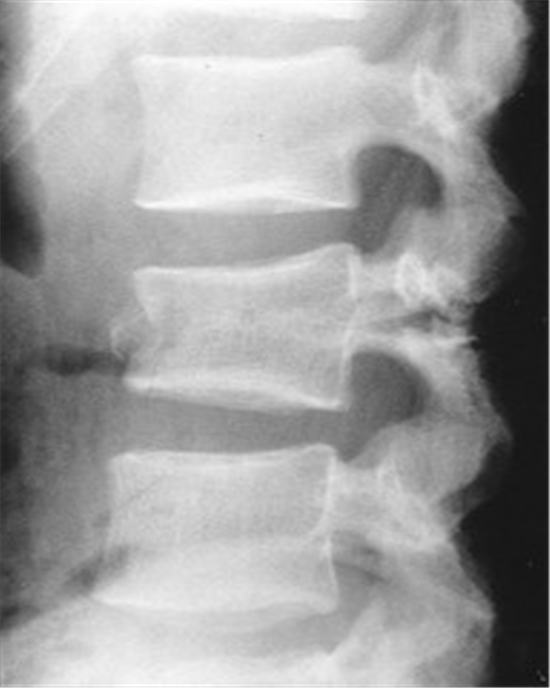

Fractured spine

Fractured spine 140 фотографий